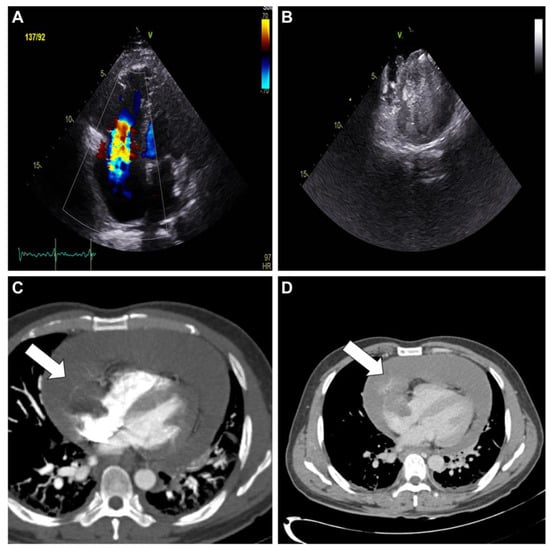

Figure 2. A cardiac magnetic resonance scan revealed an immobile mass (white arrow) in the right atrium extending to the pericardial space (A). The mass appeared predominantly isointense on T1-weighted images (B) and heterogeneous on T2-weighted images (C). The hemorrhagic areas within the mass exhibited increased signal intensity on T2-weighted short tau inversion recovery images (D). T1/T2 mapping revealed a long T1/long T2 profile (E,F). Histopathological examination of the endocardial biopsy of the right atrial mass was consistent with primary angiosarcoma showing high mitotic activity (39/10 high power field) and necrosis in hematoxylin and eosinophil stain. Immunohistochemical stain for specific tumor markers was positive for CD31, ERG, and CD34.

Diagnostics 13 02666 g002